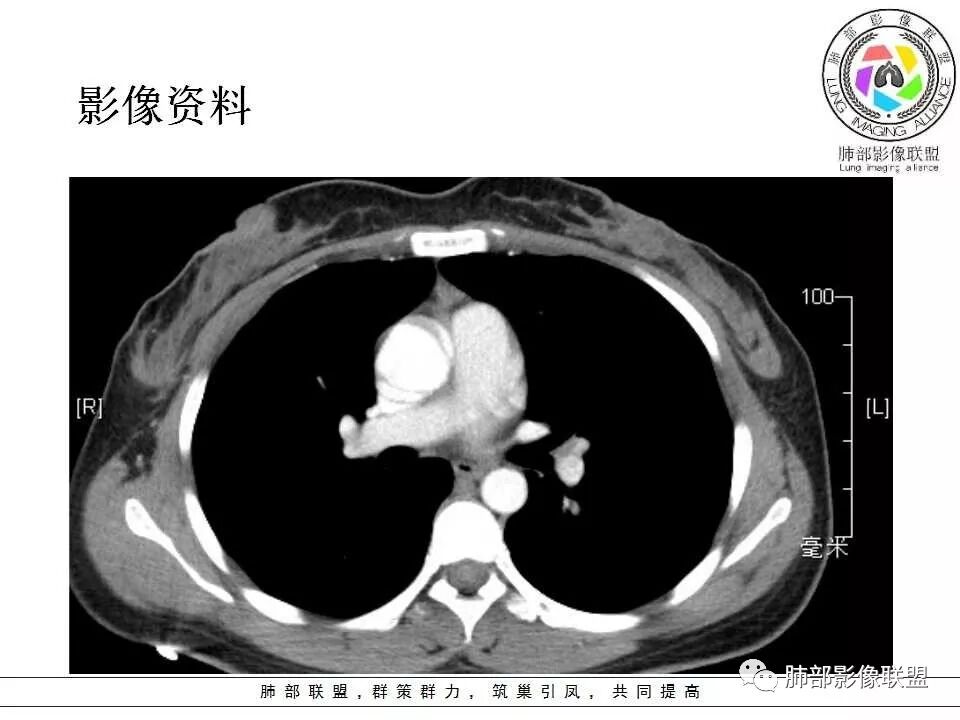

左肺门肿块,边缘光滑清晰,血管贴边,明显均匀强化,考虑PSP,鉴别类癌。

学习一下南大的诊断思路,左肺门区病灶,应该没跨叶,感觉都在上叶,强化密度均匀,边缘清晰,与支气管关系不大,常规考虑良性病变,PSP可能性大,鉴别CD,血管源性。但是一年增大怎么解释,不知道增大多少。

左肺病灶与支气管关系密切,类癌粘膜下生长,支气管略变窄,支气管外病变较大,符合冰山征表现,一年内有增长,考虑类癌,鉴别PSP,建议薄层重建。

我怎么又感觉跨叶间裂了,而且有胸膜尾征和可疑的指状突起,强化很明显,考虑SFT可能大,鉴别类癌和CD

患者中年女性,发现左肺上叶占位,随访发现体积增大。胸部CT:左肺上叶尖后段实性占位,位于支气管旁,未见支气管阻塞,病灶边界清楚,边缘光滑,增强可见病灶均匀强化,血管贴边,考虑良性病变,PSP?

左肺上叶后段紧贴斜裂结节影,支气管通畅,斜裂无移位,说明病灶来源斜裂可能,强化密度均匀,边缘清晰,考虑良性病变,PSP可能性大,鉴别CD。

患者中年女性,发现左肺上叶占位1年余入院,随访发现体积增大。胸部CT:左肺上叶尖后段近肺门及叶间裂实性类圆形结节,病灶边界清楚光滑,增强可见病灶明显均匀强化,其旁未见支气管堵塞。综合考虑良性病变,孤立性纤维瘤可能,鉴别巨大淋巴结增生症及硬化性肺细胞瘤。

中年女性,发现左肺上叶占位。胸部CT:左肺上叶尖后段孤立卵圆形实性病灶,位于支气管旁,边界清楚,边缘光滑,血管贴边,肺动脉为主征,增强扫描明显均匀强化。考虑:PSP?鉴别CD、类Ca。

青年女性,左肺门占位。定位:跨叶间裂,下叶邻近支气管推压,考虑肺外病变。影像表现:血管贴边,边缘光滑,强化均匀,考虑良性病变,PSP可能大,鉴别CD。

左肺上叶类圆形实性病灶,边缘光滑,可见血管贴边征,病灶与左肺上叶支气管关系密切,左肺动脉相对增粗,增强病灶均匀强化,常规考虑PSP,其次神经内分泌肿瘤不排除。

年轻女性,左肺门肿块,边缘光滑,密度较均匀,增强后肿块明显均匀强化,血供丰富,病史提示一年明显增大,也说明富血供,常规考虑PSP,类癌待排。

青年女性,一年前发现肺结节,复查有增大,未见近期片对比,定位:左肺上叶左肺门旁见实性类圆形结节,边界清晰光整,有部分分叶征,增强有均匀强化,与左上叶后段支气管关系不好判断,左上叶后段支气管未显示,堵塞?狭窄?需冠矢状面看看,定性:常规考虑良性或低度恶性肿瘤,典型的类癌或硬化性肺细胞瘤psp可能,神经源性或神经内分泌肿瘤、巨淋巴结增生症CD不除外,转移瘤、孤立性纤维瘤待排,建议HRCT或支气管镜检查。

年轻女性,左肺门区占位,斜裂推移未跨叶,类圆形,增强扫描明显强化,和支气管关系显示不是太清楚,感觉关系不是太密切,未见阻塞性炎症,一年后有长大,首先考虑PSP,鉴别类癌,SFT。

36岁女性,发现左肺占位1年,时有干咳。CT:左肺门(上叶尖后段?)类圆形结节,边界清,靠前边缘似有GG0,近肺门侧与血管密切接触,似有小凸起,增强见明显均匀强化,似有条片状影往肺门侧血管钻。图片有点少,病灶与支气管的关系看不清(目前的图片与支气管不密切)。随诊结节增大,整体考虑典型类癌可能性大,鉴别硬化性肺细胞瘤。